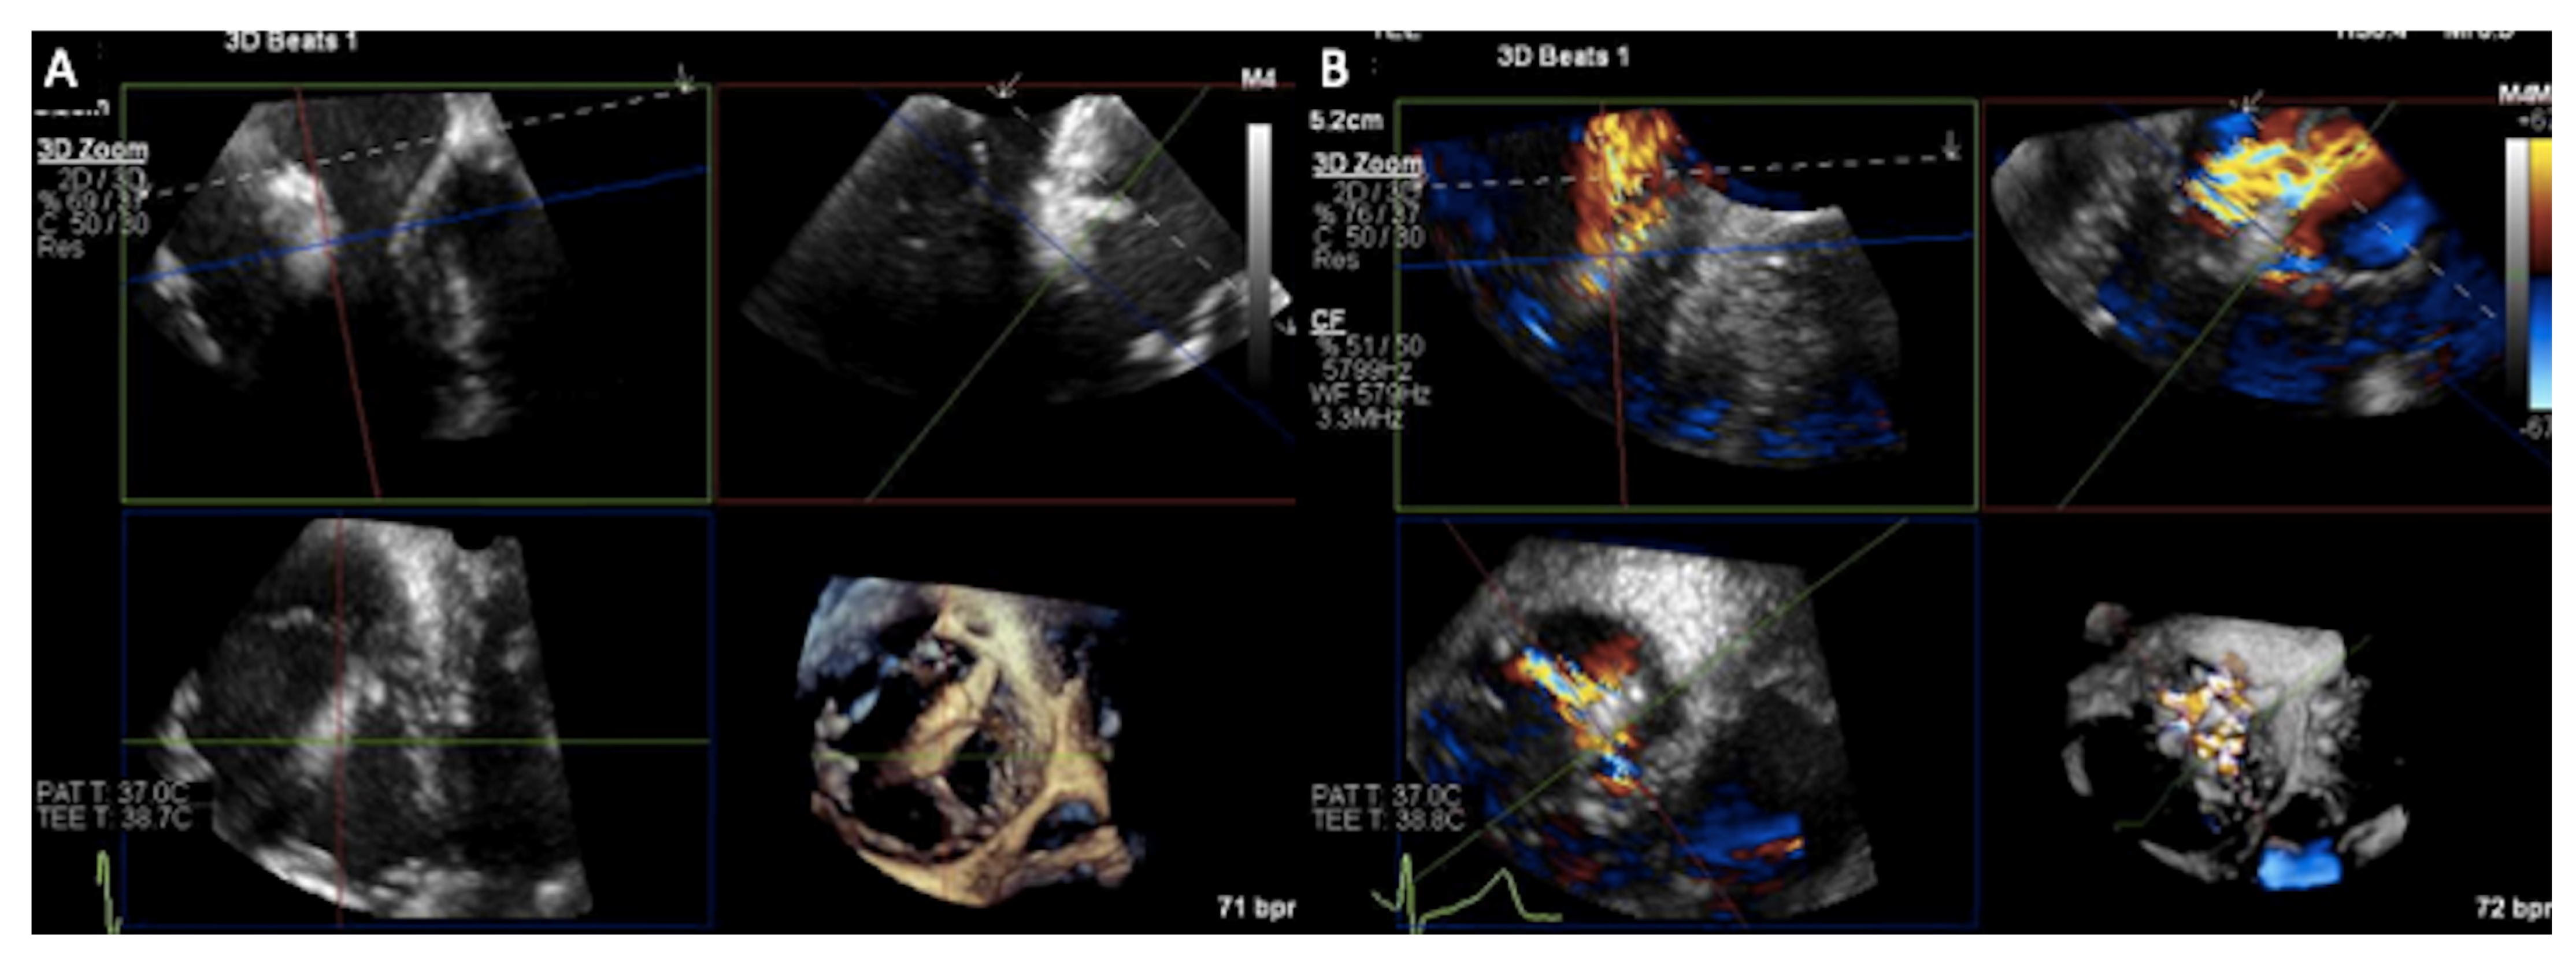

3.1. Two-Dimensional and Three-Dimensional Transesophageal Echocardiography

- Prihadi, E.A.; Delgado, V.; Hahn, R.T.; Leipsic, J.; Min, J.K.; Bax, J.J. Imaging Needs in Novel Transcatheter Tricuspid Valve Interventions. JACC Cardiovasc. Imaging 2018, 11, 736–754. [Google Scholar] [CrossRef]

- Hahn, R.T.; Saric, M.; Faletra, F.F.; Garg, R.; Gillam, L.D.; Horton, K.; Khalique, O.K.; Little, S.H.; Mackensen, G.B.; Oh, J.; et al. Recommended Standards for the Performance of Transesophageal Echocardiographic Screening for Structural Heart Intervention: From the American Society of Echocardiography. J. Am. Soc. Echocardiogr. 2021, 35, 1–76, Erratum in J. Am. Soc. Echocardiogr. 2022, 35, 447. [Google Scholar] [CrossRef] [PubMed]

- Hahn, R.T.; Kodali, S.K. State-of-the-art intra-procedural imaging for the mitral and tricuspid PASCAL Repair System. Eur. Heart J. Cardiovasc. Imaging 2022, 23, e94–e110. [Google Scholar] [CrossRef]

- Sugiura, A.; Tanaka, T.; Kavsur, R.; Oeztuerk, C.; Vogelhuber, J.; Wilde, N.; Becher, M.U.; Zimmer, S.; Nickenig, G.; Weber, M. Leaflet Configuration and Residual Tricuspid Regurgitation after Transcatheter Edge-to-Edge Tricuspid Repair. JACC Cardiovasc. Interv. 2021, 14, 2260–2270. [Google Scholar] [CrossRef] [PubMed]

- Hahn, R.T.; Nabauer, M.; Zuber, M.; Nazif, T.M.; Hausleiter, J.; Taramasso, M.; Pozzoli, A.; George, I.; Kodali, S.; Bapat, V.; et al. Intraprocedural Imaging of Transcatheter Tricuspid Valve Interventions. JACC Cardiovasc. Imaging 2019, 12, 532–553. [Google Scholar] [CrossRef]

- Ro, R.; Tang, G.H.L.; Seetharam, K.; Khera, S.; Sharma, S.K.; Kini, A.S.; Lerakis, S. Echocardiographic Imaging for Transcatheter Tricuspid Edge-to-Edge Repair. J. Am. Heart Assoc. 2020, 9, e015682. [Google Scholar] [CrossRef] [PubMed]

- Ancona, F.; Stella, S.; Taramasso, M.; Marini, C.; Latib, A.; Denti, P.; Grigioni, F.; Enriquez-Sarano, M.; Alfieri, O.; Colombo, A.; et al. Multimodality imaging of the tricuspid valve with implication for percutaneous repair approaches. Heart 2017, 103, 1073–1081. [Google Scholar] [CrossRef] [PubMed]

- Agricola, E.; Ancona, F.; Stella, S.; Rosa, I.; Marini, C.; Spartera, M.; Denti, P.; Margonato, A.; Hahn, R.T.; Alfieri, O.; et al. Use of Echocardiography for Guiding Percutaneous Tricuspid Valve Procedures. JACC Cardiovasc. Imaging 2017, 10, 1194–1198. [Google Scholar] [CrossRef]